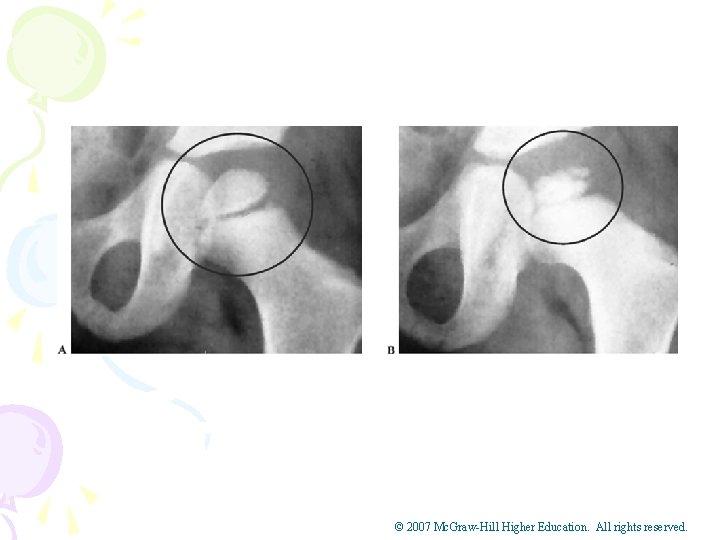

Hip Problems in Adolescent Athletes • Legg Calve’-Perthes Disease • Cause of Condition • Avascular necrosis of the femoral head in child ages 4 -10 • Articular cartilage becomes necrotic and flattens – Signs of Condition • Pain in groin that can be referred to the abdomen or knee • Limping is also typical • Varying onsets and may exhibit limited ROM © 2007 Mc. Graw-Hill Higher Education. All rights reserved.

• Legg-Calve’-Perthes Disease (continued) • Care – Bed rest to reduce chance of chronic condition – Brace to avoid direct weight bearing – Early treatment and head may reossify and revascularize • Complication – If not treated early, will result in illshaping and osteoarthritis in later life © 2007 Mc. Graw-Hill Higher Education. All rights reserved.